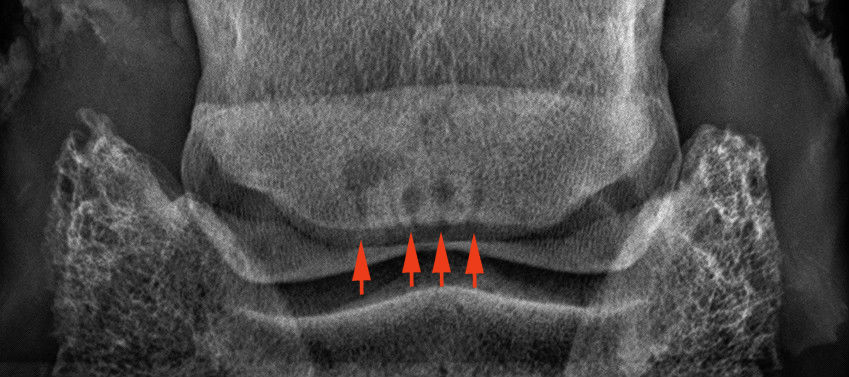

A nyírcsont vizsgálatára szolgáló un. oxspring felvétel. A nyilak a nyírcsontot mutatják.

Egészséges nyírcsont. Szabályos határai vannak, egyenletesen sötétszürke színű.